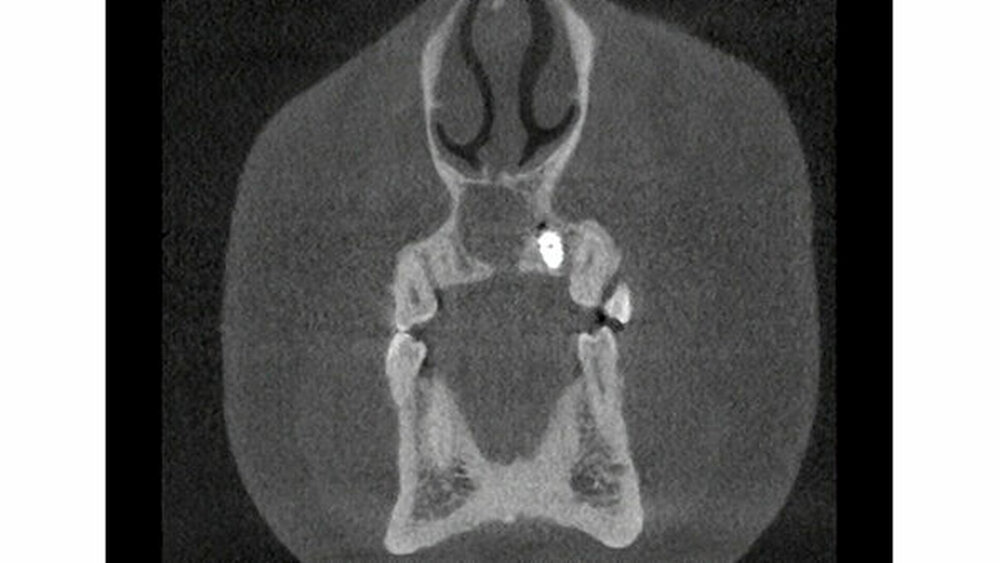

Zur weiteren Abklärung erfolgte eine dreidimensionale Bildgebung mittels DVT (Abbildung 3). Hier zeigte sich eine gut abgrenzbare Raumforderung im Bereich der Oberkieferfront mit Kontakt zum Canalis incisivus. Es wurde eine Zystektomie mit palatinaler Aufklappung in Kombination mit einer Beckenkammaugmentation durchgeführt. Intraoperativ kam es nach Injektion der Lokalanästhesie zu einem Spontanprolaps eines Idoformstreifens palatinal (Abbbildung 4).